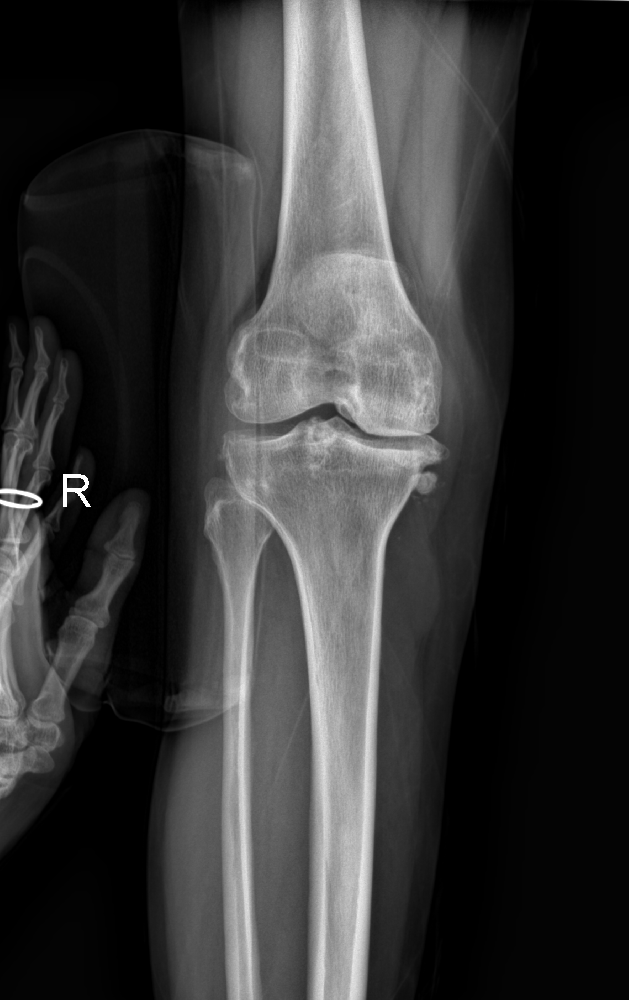

為了擺脫這長期的苦痛,賈紀花選擇了市中區(qū)誠德骨科醫(yī)院入院接受更為全面的檢查。在完成檢查后,醫(yī)生決定為她實施右膝關(guān)節(jié)內(nèi)側(cè)活動平臺單髁置換術(shù)。手術(shù)完成后,賈紀花術(shù)后恢復良好,再次嘗到了疼痛消失的滋味。